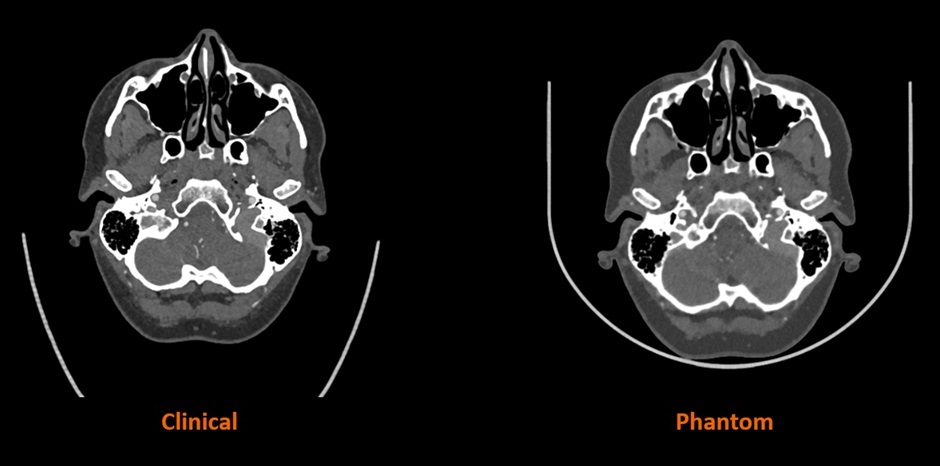

据悉,这种防透射材料已在英国与包括CPI和博蒙特医院在内的合作伙伴开展的合作研究项目中得到应用,展现了临床和教育领域的应用潜力。诸如脑血管造影模型等不透射线的3D打印模型,有助于提高培训的逼真度,并为影像研究创造可重复的环境。

Stratasys 与西门子医疗合作的早期研究结果表明,RadioMatrix 人体模型能够以极高的精度在 CT 成像中复制人体组织,即使在灰质和静脉等敏感区域,偏差也仅为 1 个亨氏单位 (HU)。结合Stratasys 的数字解剖技术和先进的成像算法,最终生成的模型既保留了解剖和病理细节,又为基于尸体的培训提供了一种一致且符合伦理的替代方案。预计这些模型将帮助放射科医生改进和验证 CT 扫描方案,同时加快高级成像算法的创建,从而实现更准确的诊断和治疗计划。

△人体CT扫描与Stratasys公司3D打印模型CT扫描对比。图片来自Stratasys公司。